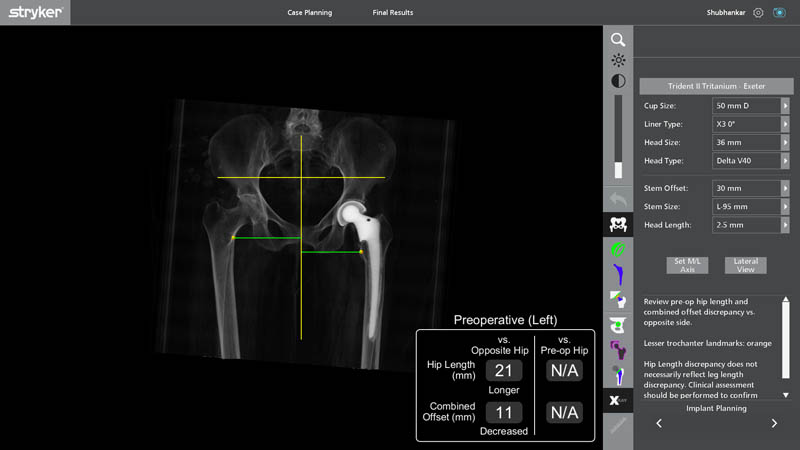

Preoperative Planning

- 3D Preoperative Planning with Segmentation

o Detailed separation (segmentation) of bone, old implant, and soft tissue - Accurate Assessment of Bone Loss